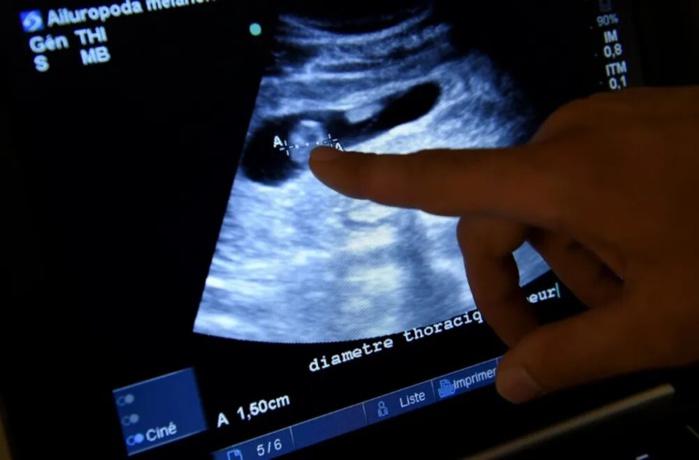

Selon le communiqué, ce dispositif permet d’obtenir en quelques jours un diagnostic fiable de l’endométriose, une maladie qui touche plus de 180 millions de femmes dans le monde, grâce à un simple prélèvement de la salive.